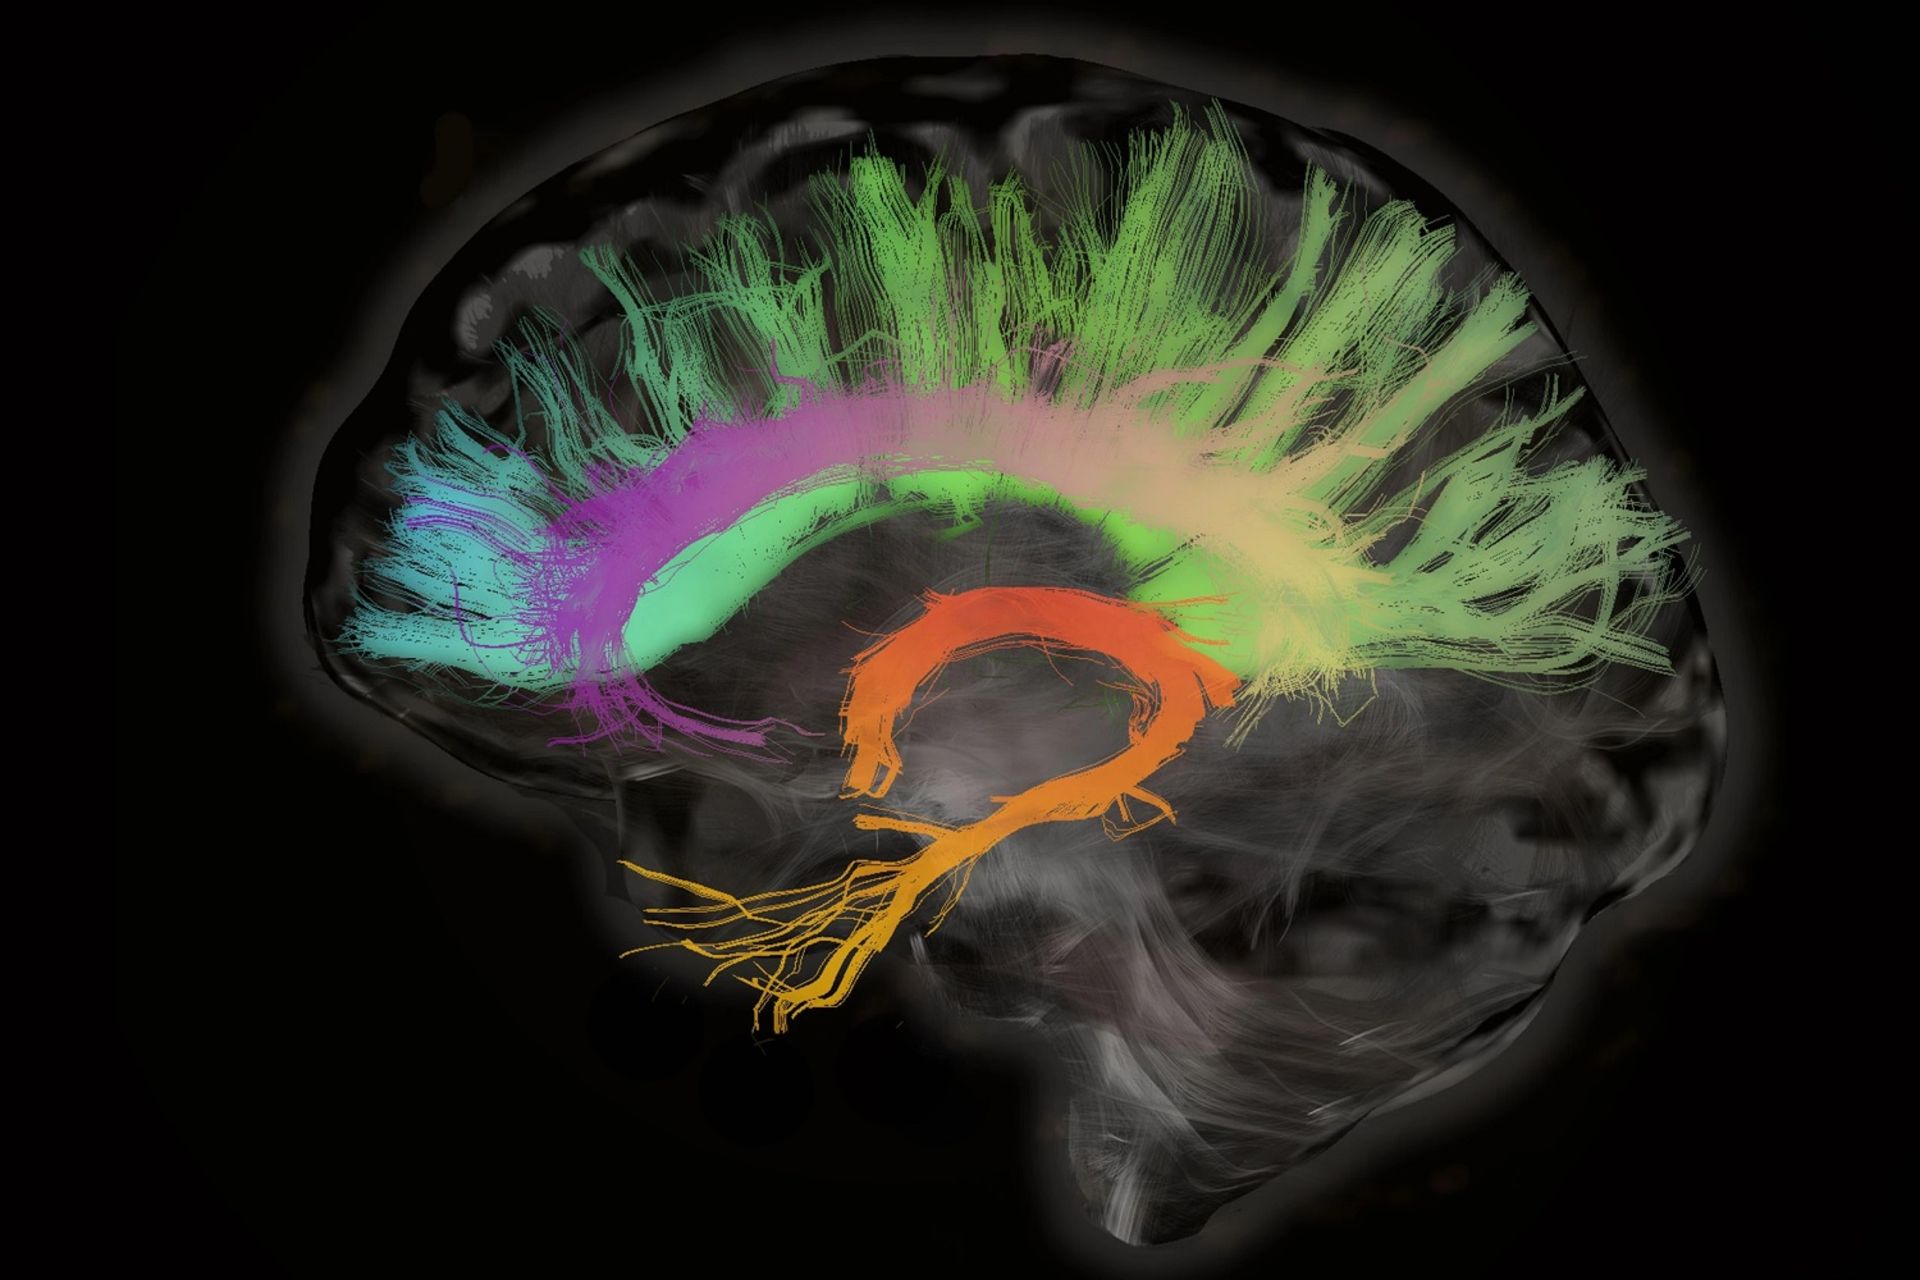

انواع مختلف حافظه توسط بخشهای مختلف مغز کنترل میشود